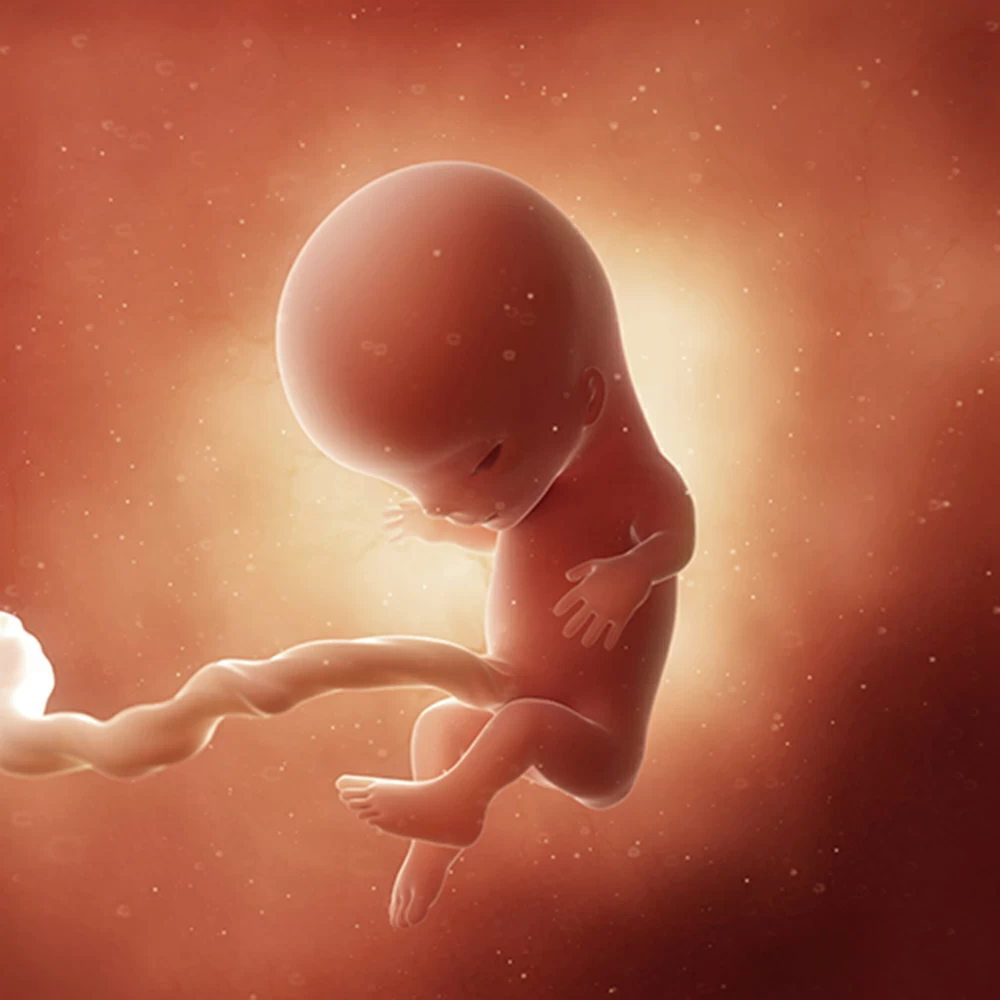

Дневник беременности